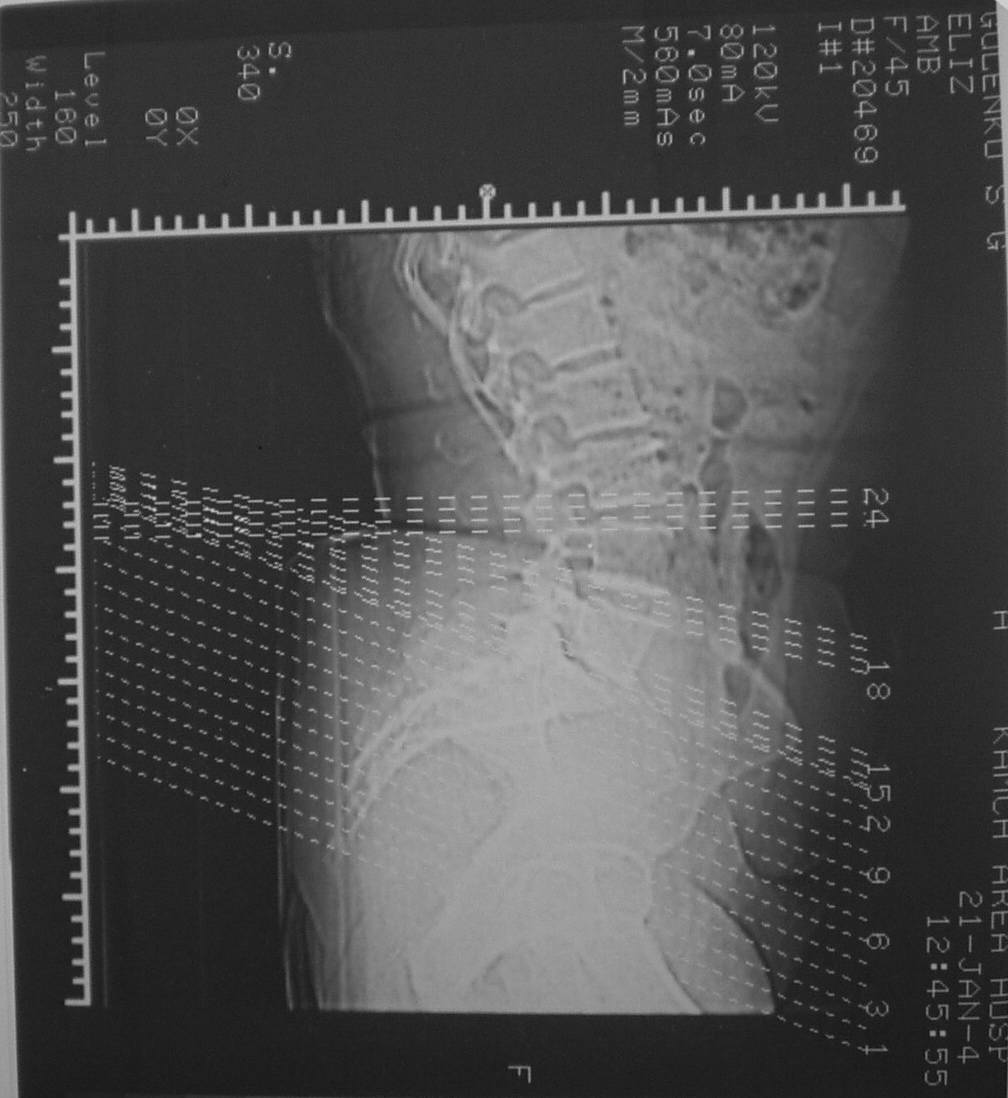

Из анамнеза: в ноябре 2002г. оступилась,упалана трап самолета (на верхней площадке, сразу при выходе из салона) на правый тазобедренный сустав, а затем - вниз на землю на ноги и ягодицы. Потеряла сознание от боли. Доставлена в больницу по месту жительства, лечилась консервативно с диагнозом кокцигодиния.На рентгенограмме от 27.11.02г. вывиха копчика не определяется (снимок идентичен представленной R-грамме от28.11.03г., кроме этого есть нормальная R-грамма копчика в боковой проекции).Через три недели стала ходить, но привести правую ногу в тазобедренном суставе не могла. Сейчас ходит отведя кнаружи правое бедро и голень, как ножку циркуля (фото 1). Неврологических нарушений нет. По просьбе врачаможет на 30-40 секунд поставить ноги вместе (фото 2). При этом испытывает сильную тянущую боль и ощущение "вывернутости" в правом тазобедренном суставе. Эти ощущения заставляют вновь отвести бедро. В положении лежа разогнуть бедро полностью не может из-за болей в ягодичной мышце (фото 3). Сгибание также ограничено из-за болей (фото 4). Отведение в положении лежа возможно в том же объеме, что и стоя (фото 5). Заподозрен старый разрыв правого крестцово-подвздошного сочленения.Выполнено R-исследование и КТ(в приложении). По-поводу деформации лонного сочленения выяснен гинекологический анамнез. Роды одни, нормальные в 22 года. Из роддома выписана на 8 сутки, нарушения походки не было, R-графия таза не проводилась. Вопросы на обсуждение: 1. Диагноз либо алгоритм дальнейшего обследования. 2. Лечебная тактика (в первую очередь возможность и целесообразность оперативного лечения).

Отсутствие изменений сустава на КТ и обычных рентгенограммах, стойкие боли и ограничение подвижности в суставе - симптомы, характерные для повреждения ацетабулярной губы. ЯМР с контрастом или без должны прояснить картину.

Уважаемый Юрий Алексеевич, сделаны ли пациентке более дистальные срезы КТ с захватом области тазобедренного сустава? Учитывая давность травмы, могли присоединиться и дистрофические процессы в субхондральной кости головки и впадины. Изменения в капсуле будут хорошо видны на УЗИ, особенно в сравнении со здоровой стороной. Эффективность лечебно-диагностического введения гормональных препаратов, на мой взгляд, сомнительна ввиду давности патологического состояния. При такой стойкой и давней контрактуре без операции вряд ли можно обойтись. Под наркозом амплитуда на разгибание должна увеличиться, усилить эффект можно тено-миотомиями заинтересованных групп мышц, капсулотомией + в послеоперационном периоде хорошее консервативное противовоспатлительное лечение с укладками на разгибание.Что мешает приведению пока не ясно, во встретившихся в нашей работе аналогичных ситуациях причиной был формирующийся медиальный остеофит головки, выталкивающий её из впадины.